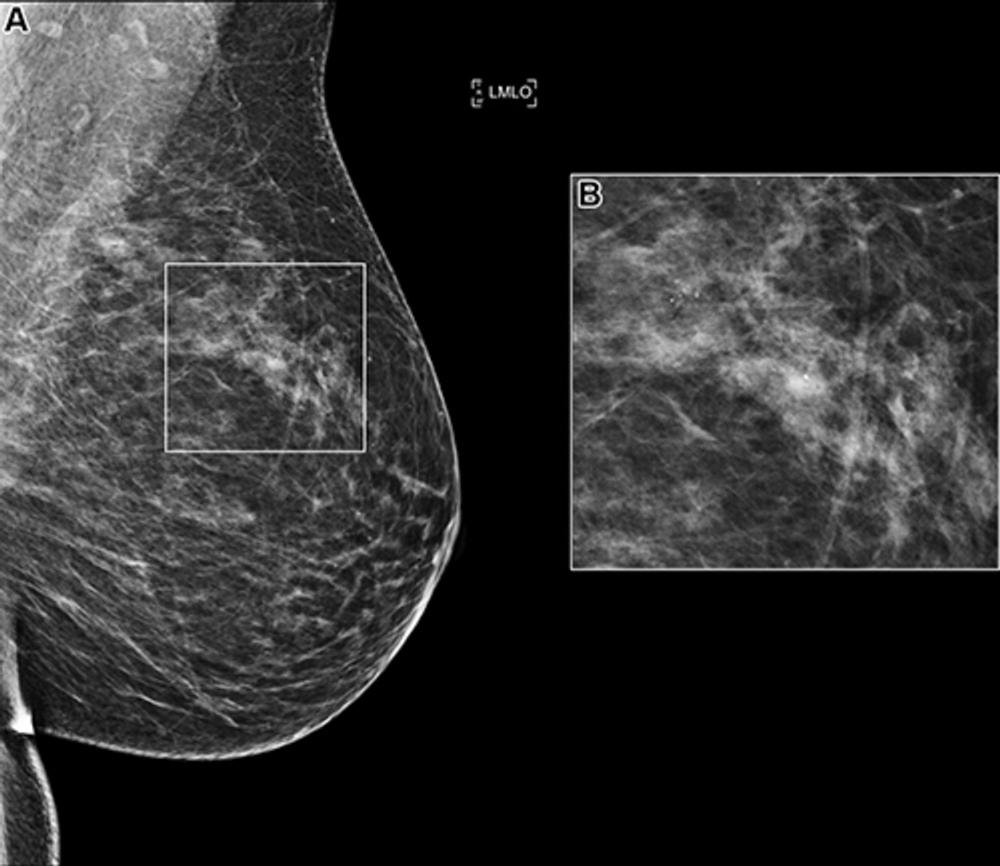

Figure 1. (A) Left mediolateral oblique (LMLO) mammogram in a 58-year-old woman with an area of microcalcification (box). (B) Magnified view (2.2×) of the box in A. This case was recalled by all of the top 10 artificial intelligence algorithms but was found to be benign at biopsy analysis.